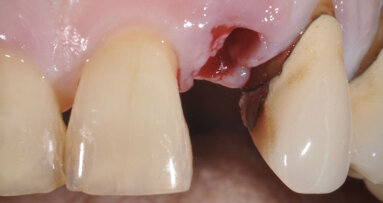

Dopo l’osteointegrazione degli impianti, i denti 17 e 27, che non potevano essere conservati, sono stati estratti. Dopo otto settimane di guarigione, la protesi provvisoria è stata rimossa e gli abutments Uni EV sono stati scoperti per prendere l’impronta finale (Fig. 10).